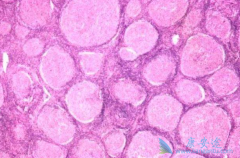

硼替佐米的适应症是哪些? 多发性骨髓瘤 :本品可联合美法仑和泼尼松(MP方案)用于既往未经治疗的且不适合大剂量化疗和骨髓抑制的多发性骨髓瘤患者的治疗;或单药用于多发性骨髓瘤患者最少接受过一种或者是一种以上治疗后复发。   套细胞淋巴瘤:本品 ...